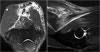

This is a nice example of subacute denervation.

Notice on the T1W-image that there is no atrophy. Only edema on the T2W-image.

This was due to proximal radial neuropathy.